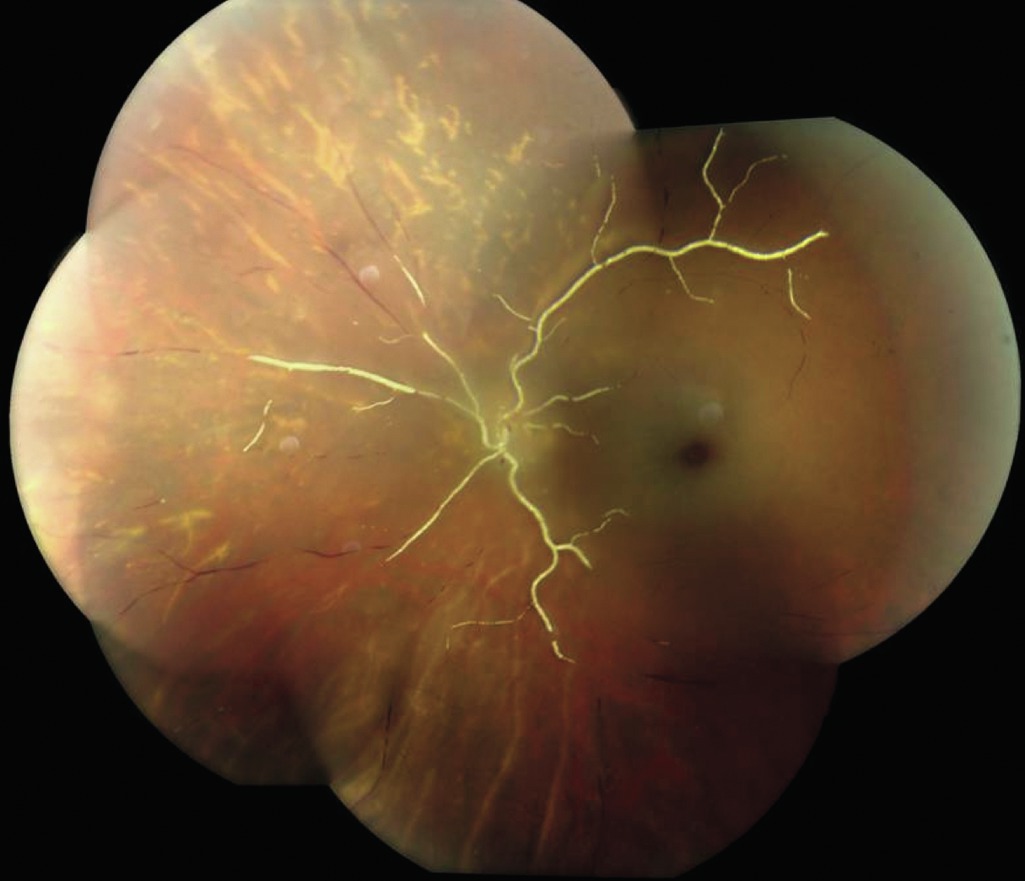

Figure 6-12

Œdème maculaire cystoïde (OMC) secondaire à une OVCR avant et après le traitement. A. OCT spectral-domain montrant un OMC sévère avec détachement fovéolaire chez un patient présentant une OVCR non ischémique. L'acuité visuelle était de 1/10. B. Un mois après une injection intravitréenne de bévacizumab, 1,25 mg, les lésions kystiques et le détachement fovéolaire ont disparu, et l'acuité visuelle est à 8/10.